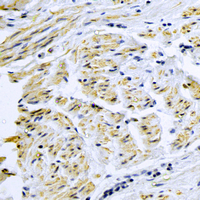

IHC (Immunohiostchemistry)

(Immunohistochemical analysis of Smooth Muscle Actin staining in human lung cancer formalin fixed paraffin embedded tissue section. The section was pre-treated using heat mediated antigen retrieval with sodium citrate buffer (pH 6.0). The section was then incubated with the antibody at room temperature and detected using an HRP conjugated compact polymer system. DAB was used as the chromogen. The section was then counterstained with haematoxylin and mounted with DPX.)